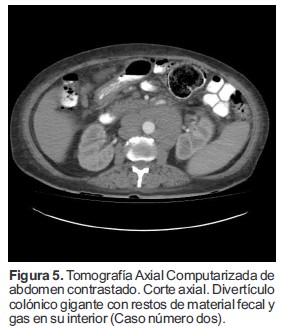

La TAC reportó múltiples imágenes diverticulares en el colon (Figura 4), se observó una imagen, un divertículo gigante del colon localizado hacia la unión del colon transverso con el ángulo esplénico el cual medía 6.0 cm de diámetro y se encontraba opacificado con restos de materia fecal y gas sin mayores signos de sobreinfección (Figura 5).

Figura 5. Tomografía Axial Computarizada de abdomen contrastado. Corte axial. Divertículo colónico gigante con restos de material fecal y gas en su interior (Caso número dos).